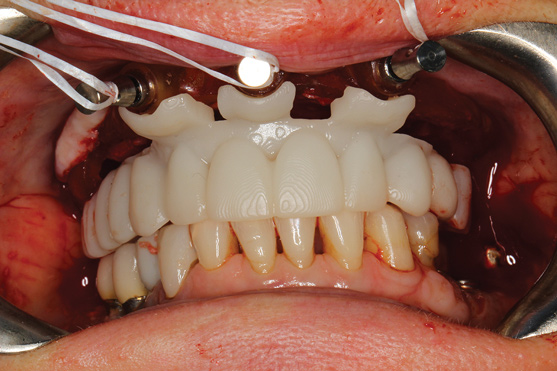

The workflow described in this case is just one example, and there are numerous ways to achieve the same goal. This particular workflow is relatively easy to execute and efficient from the standpoint of planning, fabrication, and clinical application. Figure 11 and Figure 12 demonstrate the accurate placement of the implants as can be seen by the copings exiting directly into the openings in the printed provisional. The provisional was indexed and the copings picked-up by injecting a provisional bisacryl composite resin. The finished 3D-printed provisional was characterized with pink composite and fixated to the implants with abutment screws, and the access holes were sealed with sterilized teflon tape and composite resin (Figure 13).

Fig 11. Implants with telescopic copings ready for pick-up.

Figure 11

Fig 12. Provisional seated over implant copings.

Figure 12